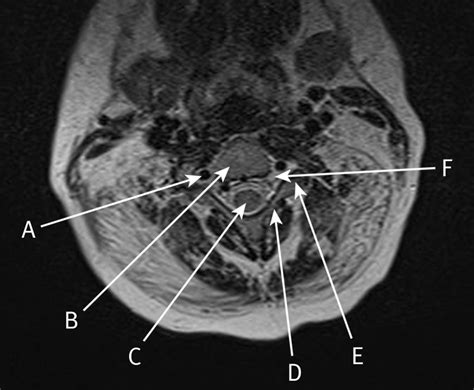

• normal cervical mri axial